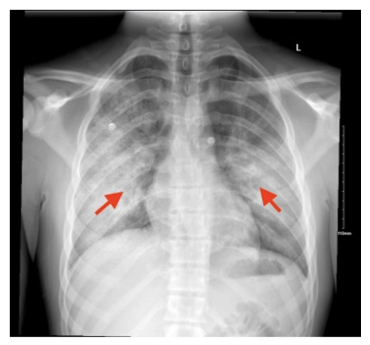

图:胸部X光片(CXR)前后位显示双侧肺泡实变,提示炎症或感染性病变取代了含气腔隙(红色箭头所示)

患者因咳嗽加重2周、痰中带血及发热就诊于急诊科,1周前曾因甲型流感合并细菌性肺炎在外院住院,接受头孢曲松、阿奇霉素及奥司他韦治疗,出院后继续口服抗生素完成疗程,但症状未缓解。入院查体可见黏膜干燥,静息血氧饱和度88%,心率107次/分,体温38.2℃,双肺底可闻及湿啰音;胸部X线片显示双肺混浊影较前加重,心电图正常,经胸超声心动图未见心脏结构异常,左心室射血分数62%(儿科正常范围55%-90%)。